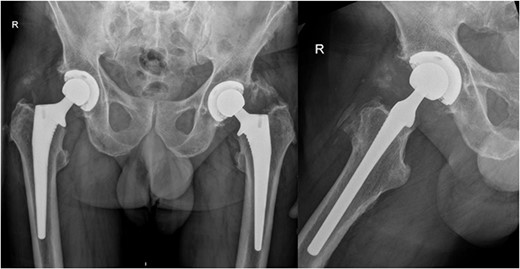

Our patient is a 74-year-old male who underwent primary total hip replacement for right hip pain. This was performed using a collared, fully hydroxyapatite-coated, uncemented stem, as well as an uncemented acetabular component with a ceramic-in-polyethylene bearing surface (Corail-Pinnacle, Depuy-Synthes, IN, USA). His recovery was uneventful until 6 weeks postoperatively when he presented to his routine outpatient appointment with significant erythema, swelling, and tenderness over his right hip wound. This was associated with difficulty weightbearing on the operative side due to discomfort. His background medical history included polymyalgia rheumatica for which he took Methotrexate 7.5 mg weekly, Folic acid 5 mg weekly, Celecoxib 200 mg BD, and pre-diabetes which was diet controlled. His other medical history included prostate cancer in remission since 2012, renal calculi, dyslipidaemia, and hypertension. He had a contralateral total hip replacement performed in 2020 (Fig. 1). He had no known drug allergies. At baseline, he was independently mobile. He was a non-smoker and non-drinker.

Preoperative AP pelvis and lateral right hip radiographs of our patient showing right hip osteoarthritis and previous left THR in situ.